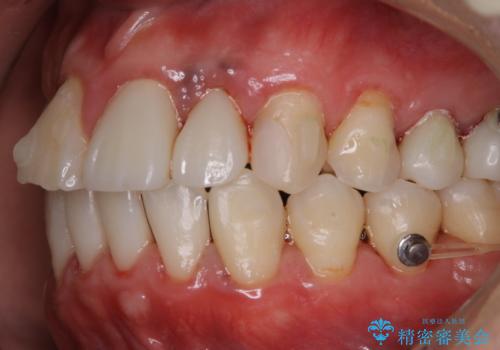

インビザライン治療中には、歯の表面にアタッチメント(効率的に歯の移動をするもの)を設定します。そのため歯ブラシでは届きにくい細かい部分などに、歯石や着色がついてしまうことがあります。着色などを放置していると、着色なのか、虫歯なのかの判別もしずらく正確にお口の中の状態を診断できません。

矯正治療中も定期的に歯科医院にてPMTCを受けて、お口のケアを行うことをおすすめします。